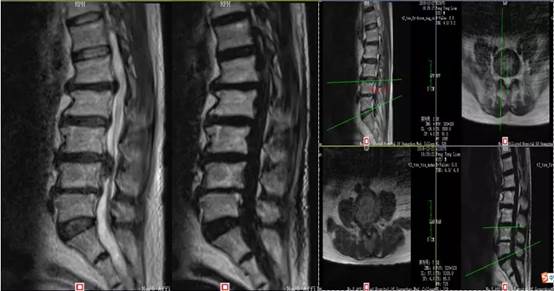

随后,给彭叔做了影像学检查,发现他存在腰椎退行性变;L3/4椎间盘突出;L4/5椎间盘膨出,L2/3、L5/S1椎间盘膨出。

需要注意的是,患者的腰椎:L1/2椎间盘突出,L2/3、L4/5椎间盘膨出,L3/4椎间盘明显突出并髓核脱出,对应水平硬膜囊前缘受压,L2、L4双侧神经根明显受压,骨性椎管继发性狭窄。